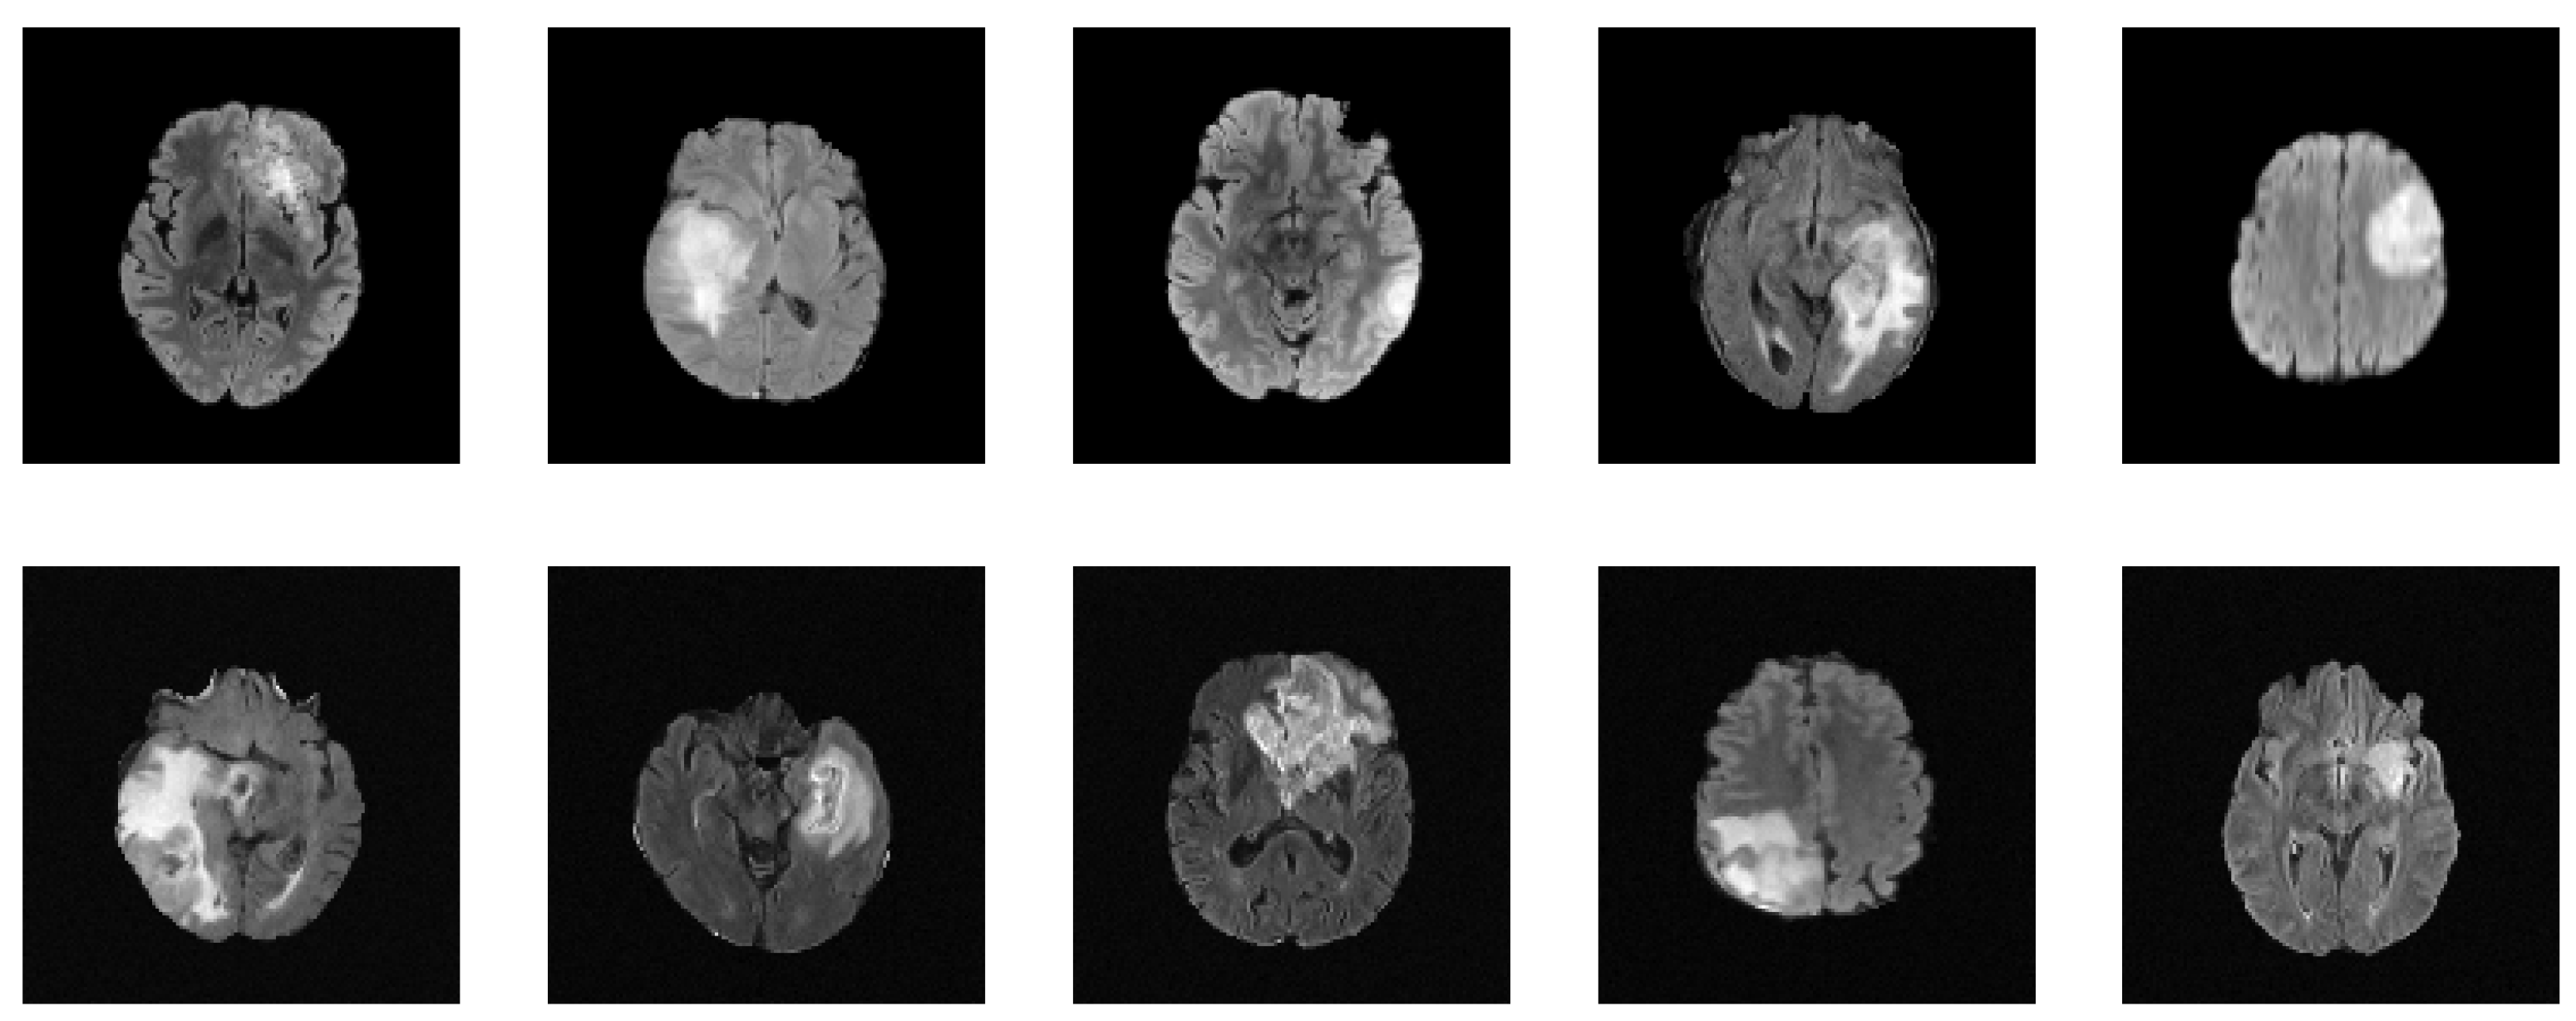

Figure 4.

Synthesized MRIs using a diffusion-based probabilistic model (DDPM) [20] trained on the BraTS2020 dataset. The first row shows a sample of original images, while the second row shows a sample of synthesized images generated using the DDPM.